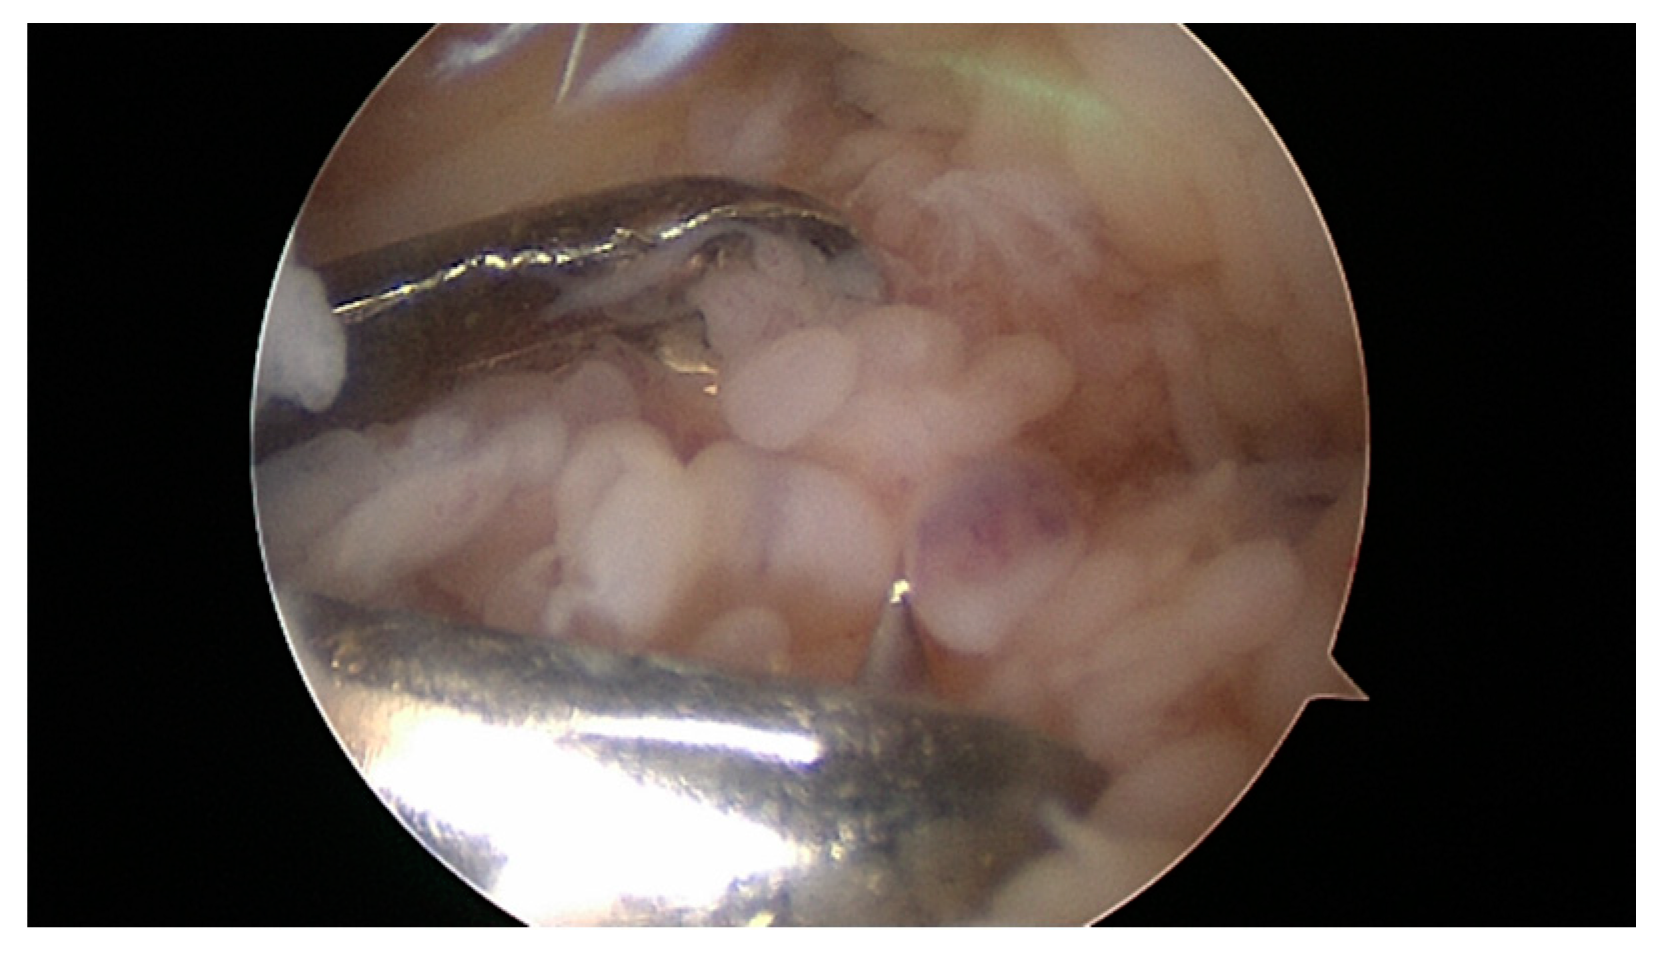

- Lipina, M.; Makarov, M.; Mukhanov, V.; Karpashevich, A.; Maglevaniy, S.; Amirdjaпova, V.; Archipov, S. Arthroscopic synovectomy of the knee joint for rheumatoid arthritis. Int. Orthop. 2019, 43, 1859–1863. [Google Scholar] [CrossRef] [PubMed]

- Kerschbaumer, F.; Kandziora, F.; Herresthal, J.; Hertel, A.; Hör, G. Combined arthroscopic and radiation synovectomy in rheumatoid arthritis. Orthopade 1998, 27, 188–196. [Google Scholar] [CrossRef] [PubMed]

- Maderbacher, G.; Greimel, F.; Schaumburger, J.; Grifka, J.; Baier, C. The knee joint in rheumatoid arthritis-current orthopaedic surgical treatment options. Z. Rheumatol. 2018, 77, 882–888. [Google Scholar] [CrossRef] [PubMed]

- Chalmers, P.N.; Sherman, S.L.; Raphael, B.S.; Su, E.P. Rheumatoid Synovectomy: Does the Surgical Approach Matter? Clin. Orthop. Relat. Res. 2011, 469, 2062–2071. [Google Scholar] [CrossRef] [PubMed]

- Carl, H.D.; Swoboda, B. Effectiveness of arthroscopic synovectomy in rheumatoid arthritis. Z. Rheumatol. 2008, 67, 485–490. [Google Scholar] [CrossRef]